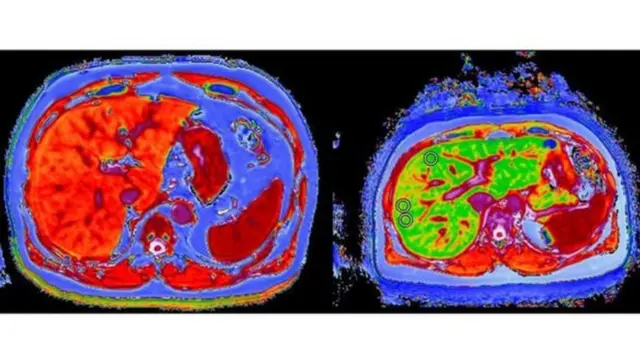

وأجرى علماء في جامعة أوكسفورد دراسة المسح الطبي للكبد بتقنيات جديدة للرنين المغناطيسي، وأُعلنت النتائج في المؤتمر السنوي الدولي للكبد في باريس.

صدر الصورة، PERSPECTUM DIAGNOSTICS

واعتمد الباحثون في جامعة أوكسفورد على نوع جديد من برمجيات التحليل المبتكرة في إجراء الرنين المغناطيسي، تسمى المسح متعدد المستويات للكبد LiverMultiScan، طورتها شركة أبحاث برسبكتم دايغونستيكس Perspectum Diagnositics، والتي تأسست بمشاركة جامعة أوكسفورد.

وقال :"إن عملية المسح تعطينا خريطة دقيقة عن الكبد بالكامل، بعكس الإبرة التي تأخذ عينة من منطقة واحدة من الكبد وربما لا تكون هامة".